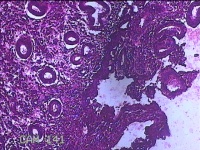

子宫腔赘生物(大)

性别

女

年龄

38岁

临床诊断

子宫内膜息肉;子宫异常出血

一般病史

月经量多数年,发现宫腔占位1个月。

标本名称

大体所见

灰白暗红色不规则肿物2.7x1.8x0.8cm一堆,切开肿物呈实性,切面灰白暗红色,质软。

图4

有那么点像子宫内膜息肉,片子这个效果,辩认起来非常困难。